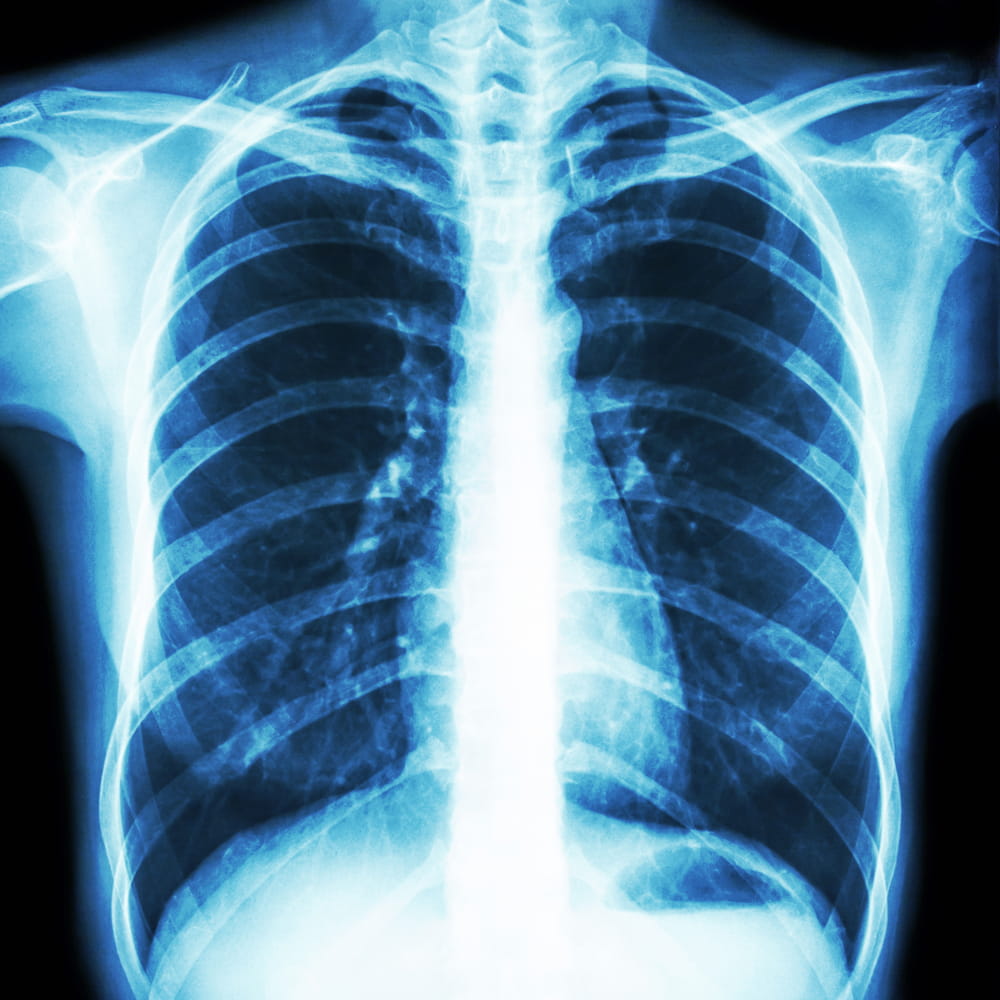

chest x-ray